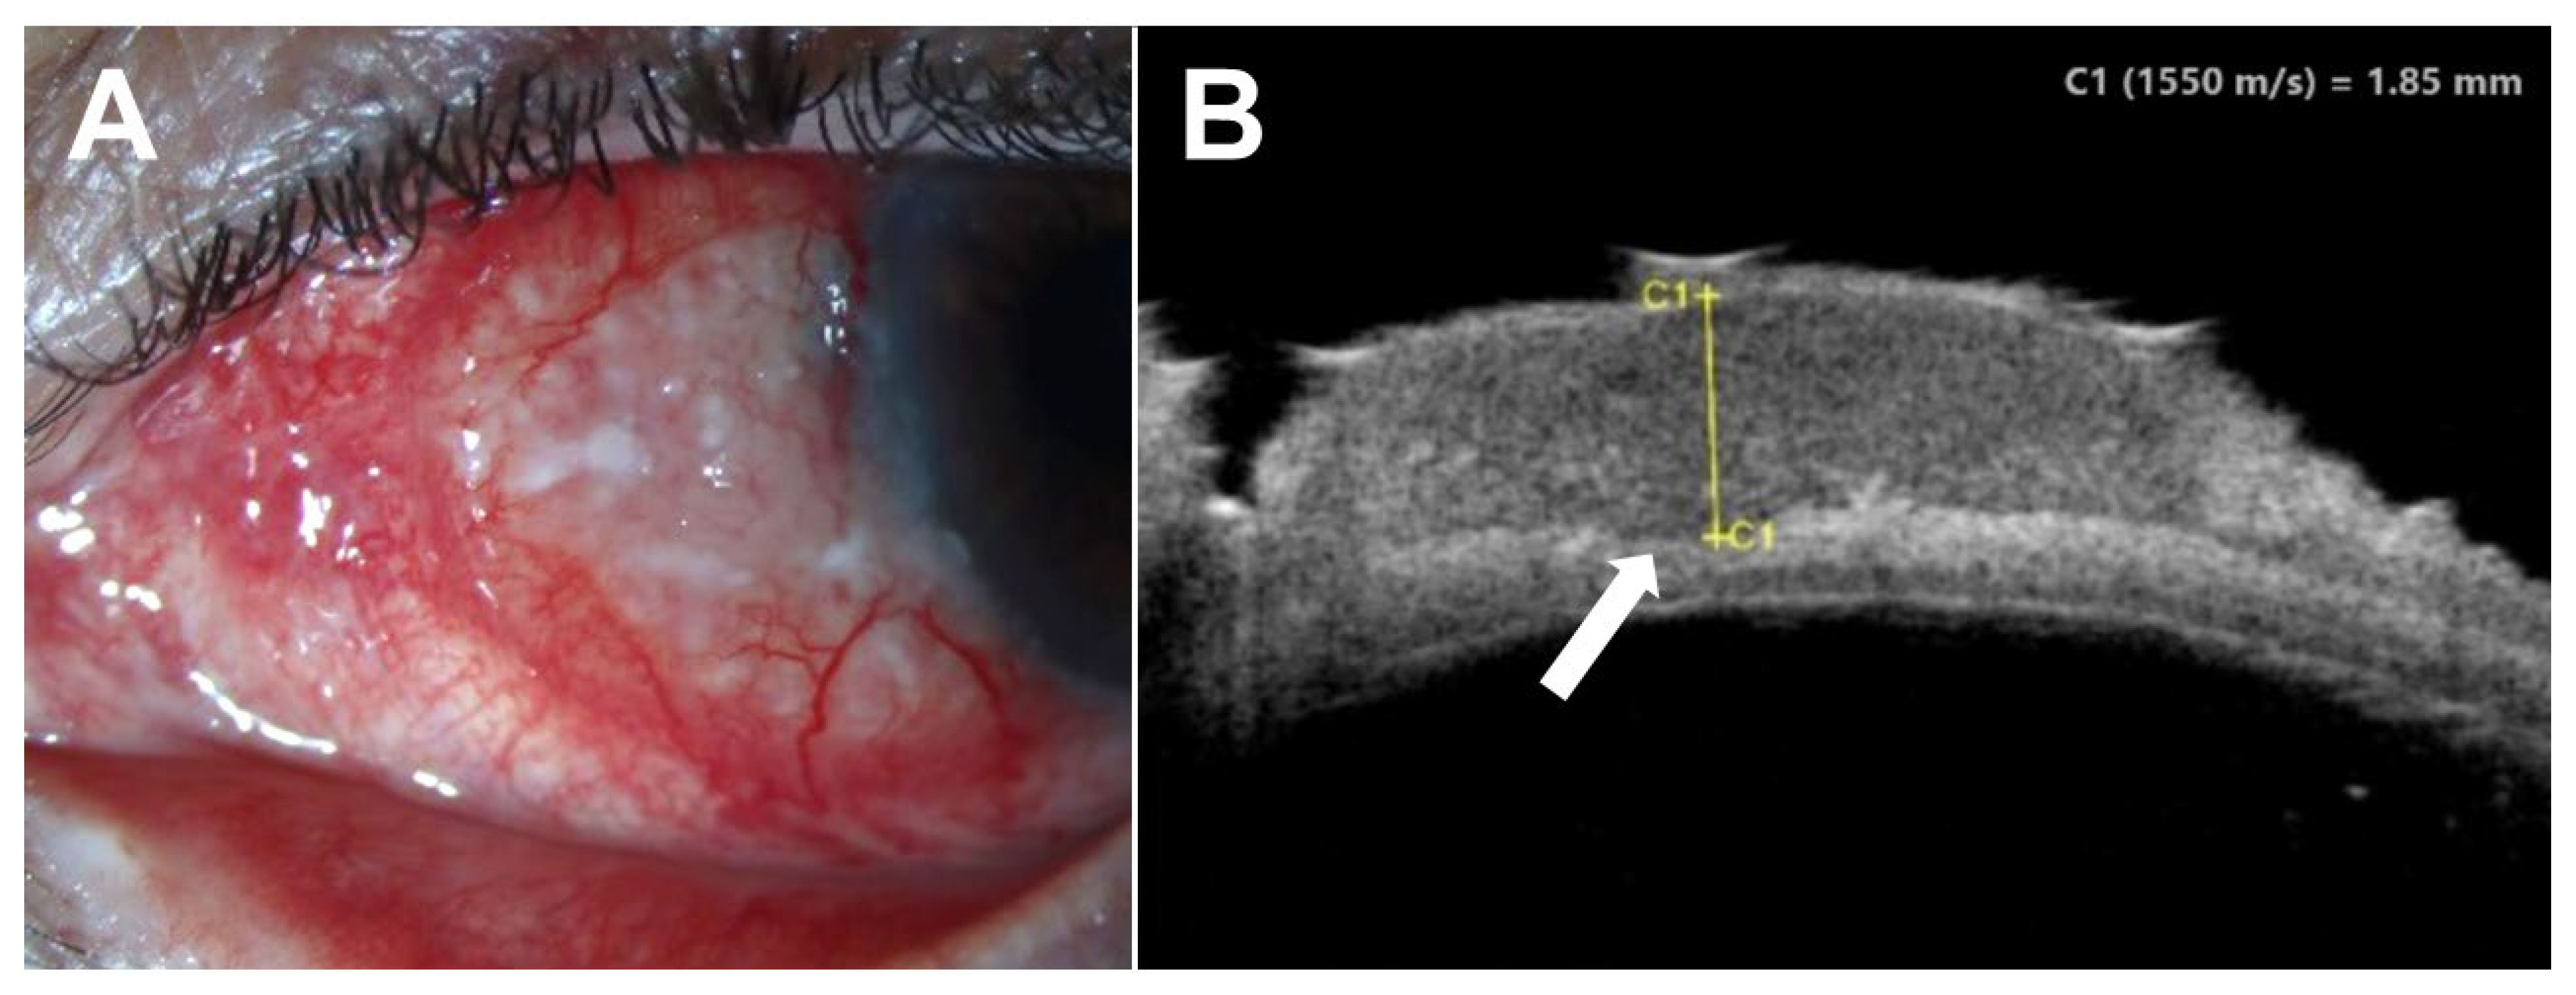

4.2. Current Applications of UBM

- Finger, P.T.; Tran, H.V.; Turbin, R.E.; Perry, H.D.; Abramson, D.H.; Chin, K.; Della Rocca, R.; Ritch, R. High-frequency ultrasonographic evaluation of conjunctival intraepithelial neoplasia and squamous cell carcinoma. Arch. Ophthalmol. 2003, 121, 168–172. [Google Scholar] [CrossRef]

- Ho, V.H.; Prager, T.C.; Diwan, H.; Prieto, V.; Esmaeli, B. Ultrasound biomicroscopy for estimation of tumor thickness for conjunctival melanoma. J. Clin. Ultrasound 2007, 35, 533–537. [Google Scholar] [CrossRef]